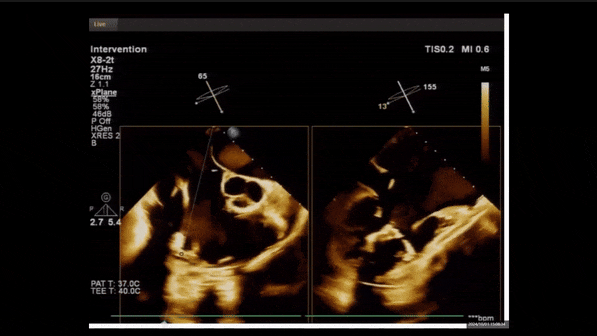

術(shù)中經(jīng)食道超聲輔助下可見(jiàn)LuX-Valve Plus夾持件抓捕瓣葉狀態(tài)良好,夾持件在位,室間隔錨定位置良好,假體瓣膜整體錨定狀態(tài)穩(wěn)固。

術(shù)前TEE評(píng)估

1、3D TEE顯示雙房及右室擴(kuò)大,右室中段直徑40mm,右室FCA 52%。三尖瓣環(huán)TAPSE 22mm,三尖瓣環(huán)左右徑49mm,三尖瓣隔葉長(zhǎng)度16mm,前葉長(zhǎng)度21mm,后葉長(zhǎng)度34mm,三尖瓣前隔gap 11mm,后隔gap 5.6mm,AP gap 12mm,診斷極重度功能性三尖瓣返流(Type I型三尖瓣:Torrential FTR 5+)。

2、彩色多普勒顯示:收縮期三尖瓣口返流束起源于后隔交界、前后葉之間及前隔交界,返流束縮流頸最大寬度27mm,三尖瓣返流口EOA=2.02cm2,返流容積124ml,收縮期三尖瓣返流峰值速度2.64m/s,返流峰值壓差28mmHg,PAPs 43mmHg,舒張期三尖瓣口平均跨瓣壓差1mmHg,肝左靜脈可見(jiàn)明顯逆向血流波。